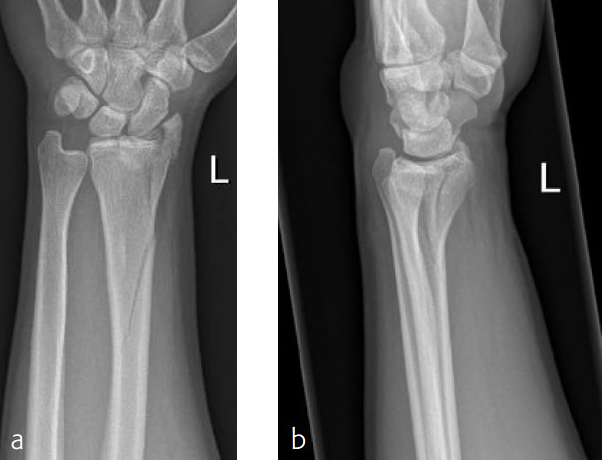

A 26-year-old man suffered a multifragmentary fracture of his left distal radius with extension into the diaphysis (AO23 C3.3) (Fig 2). The VA LCP Extra Long Two-Column plate was used for fixation (Fig 3). After initial immobilization, the plate provided a good postoperative fixation of the fracture.